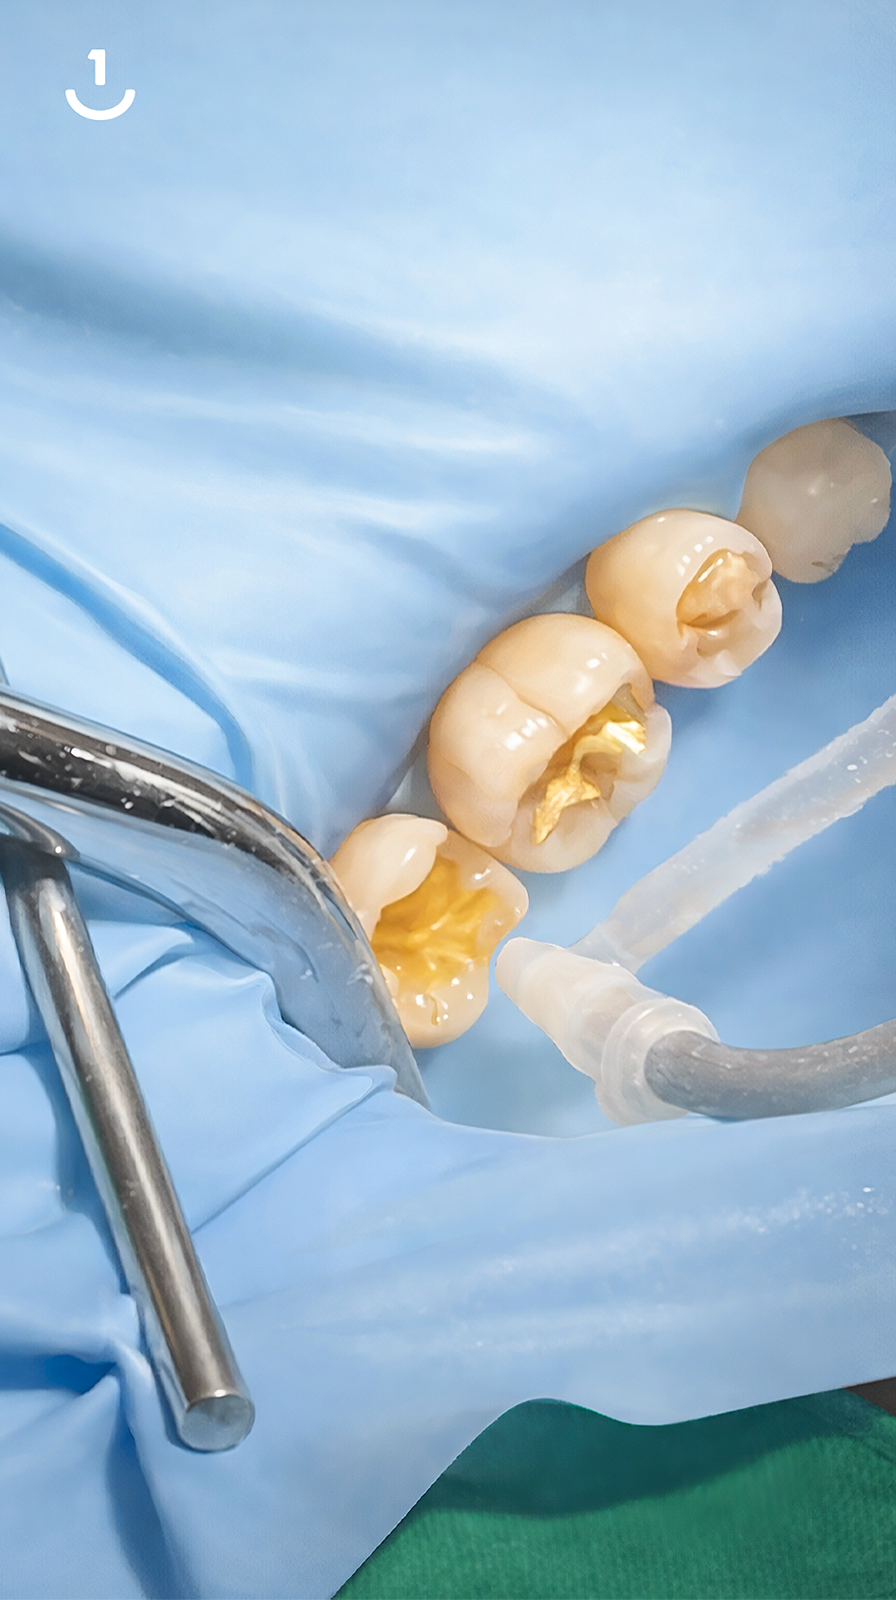

연세일등치과는 만족스러운 수복 결과를 위해, 치료 환경(러버댐)과 신중하게 재료를 선택하는 것, 두 가지를 모두 중요하게 생각합니다.

01. 치료 환경

치과 수복 과정에서 결과의 지속성을 좌우하는 중요한 요소 중 하나는

바로 건조 환경의 유지입니다. 연세일등치과는 레진빌드업 시 러버댐(Rubber Dam)

사용을 원칙으로 삼아, 수복물과 치아의 안정적인 결합을 방해할 수 있는 침(타액)과

미세한 습기, 이물질로부터 치료 부위를 보호합니다.